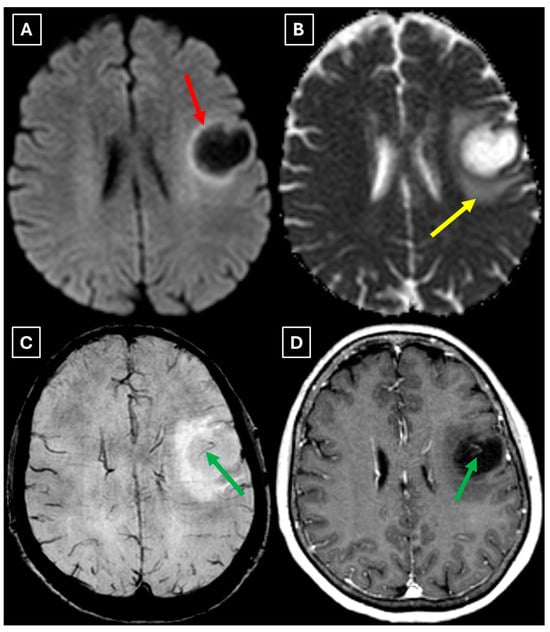

A computed tomography (CT) scan of the brain revealed a 3.5 cm hypodense lesion in the left frontal lobe with mild perifocal edema (Figure 1). Due to the unclear nature of the lesion, additional examinations were performed to rule out oncopathology, including mammography and breast ultrasound, as well as chest and abdominal CT scans, all of which were negative for oncological findings.

Figure 1. Native head CT without I/V contrast Images (A,B) show a. Hypodense lesion in the left hemisphere, basal parts of the frontal lobe. Measuring up to at least 3.5 cm in maximum size, with mild perifocal edema. Red arrow—indistinct formation.

Figure 3. MRI scan of the brain. (A): Axial trace image of diffusion-weighted imaging (DWI) shows slight diffusion restriction in the lesion wall when correlated with (B): dark signal on apparent diffusion coefficient (ADC) maps in the wall of the lesion, with no central diffusion reduction observed. (C): In the corresponding axial slice of the susceptibility-weighted imaging (SWI) sequence, there is no evidence of blood products within the lesion. (D): On the axial postcontrast T1-weighted imaging, there is no contrast enhancement in the lesion, although a central vein-like structure is observed. Red arrow—diffusion restriction, yellow arrow—perifocal vasogenic edema, green arrow—central vein sign.

We also found similarities between this case and the classical imaging features of TDLs described in the literature. Hypoattenuation on noncontrast CT corresponding to enhancing areas on MRI is another useful imaging finding in TDLs [10], which may be explained by the tissue rarefaction caused by the active demyelination rather than increased cellularity, which is seen in tumors, thereby supporting the use of MRI with noncontrast CT in TDL diagnosis. Furthermore, restricted diffusion along the lesion margin with elevated central ADC values, in contrast to neoplasms which more commonly show central diffusion restriction, have been described as a commonly presenting feature of TDLs [3,4,10], which was also observed in this case (Figure 5A,B).